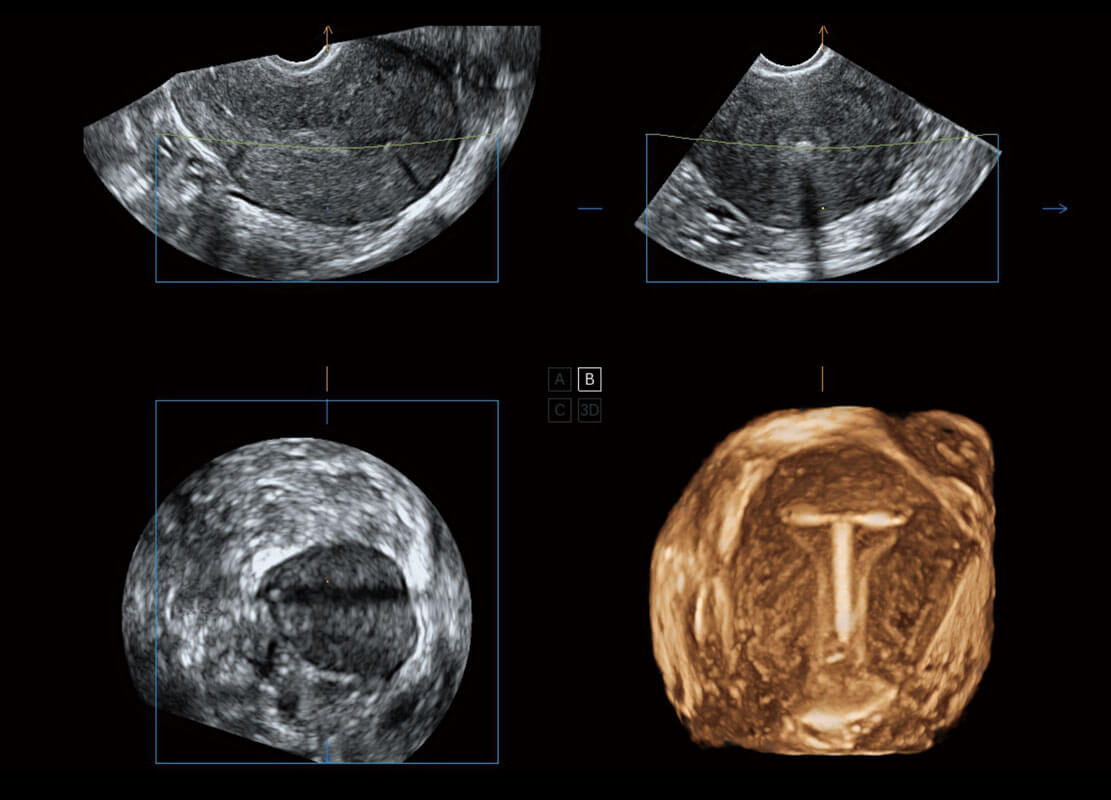

• 腔内三维-宫内节育器

• 腔内三维-光影成像

盆底超声

P60为盆底超声检查提供应用方案,多种腔内及腹部容积探头提供从二维、三维到四维的优异图像品质,实时快速三维容积数据获取,专业的测量工具包等人性化设计,为超声医生诊断提供有力保障。